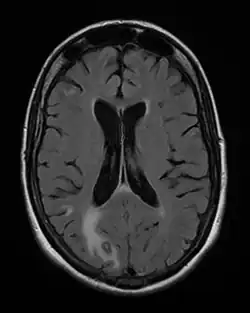

Toxoplasmose é uma doença parasitária causada pelo protozoário Toxoplasma gondii.[4] As infeções de toxoplasmose geralmente não causam sintomas óbvios em adultos.[2] Em alguns casos pode ocorrer síndrome gripal ligeira durante algumas semanas ou meses, com sintomas como dor muscular e sensibilidade nos gânglios linfáticos.[1] Numa pequena percentagem de pessoas podem-se desenvolver problemas de visão.[1] No sul do Brasil, segundo estudos iniciados na década de 1990, uma parcela significativa da população teve contato com o Toxoplasma gondii (cerca de 80 %), causando lesões oculares que podem causar a cegueira em um grande número de pessoas (17,7 %)[8]. Em pessoas imunossuprimidas, podem ocorrer sintomas graves, como crise epilépticas ou falta de coordenação motora.[1] Quando a primeira infeção ocorre durante a gravidez, a doença pode ser transmitida de mãe para filho pela placenta, uma condição denominada toxoplasmose congénita.[1] A toxoplasmose congénita está associada a morte fetal e aborto espontâneo e, em crianças, está associada a déficits neurológicos, neurocognitivos e corioretinite.[3]

Progressão e sintomas

Se a infecção se der durante a gravidez (o que ocorre em 0,5% das gestações), os parasitas podem atravessar a placenta e infectar o feto, o que pode levar a abortos e a malformações em um terço dos casos, malformações como hidrocefalia, podendo também ocorrer neuropatias e oftalmopatias na criança como défices neurológicos e cegueira, mas se a infecção tiver sido antes do início da gravidez não há qualquer perigo, mesmo que existam cistos.[26]

Os cistos contêm uma forma infectante do parasito, que é o bradizoíto, e em vez de se reproduzir rapidamente, formaram antes estruturas derivadas da célula que infectou, forte e resistente, cheia de liquido e onde o parasita se reproduz lentamente. Os cistos crescem e podem afetar negativamente as estruturas em que se situam, mais frequentemente músculos, o cérebro, no coração ou na retina, podendo levar a alterações neurológicas, problemas cardíacos ou cegueira, mas geralmente sem efeitos nefastos. Os cistos permanecem viáveis por muitos anos, mas não se disseminam devido à imunidade eficaz ganha pelo portador, inclusive contra mais oocitos que possam ser ingeridos. Se o indivíduo desenvolver ou for medicado para imunodeficiência, como após transplantes de órgãos, doenças auto-imunes ou na SIDA/AIDS, as formas ativas podem ser reativadas a partir dos cistos, dando origem a problemas sérios, com sintomas como exantemas (pele vermelha), pneumonia, meningoencefalite com danos no cérebro e miocardite, com mortalidade alta.